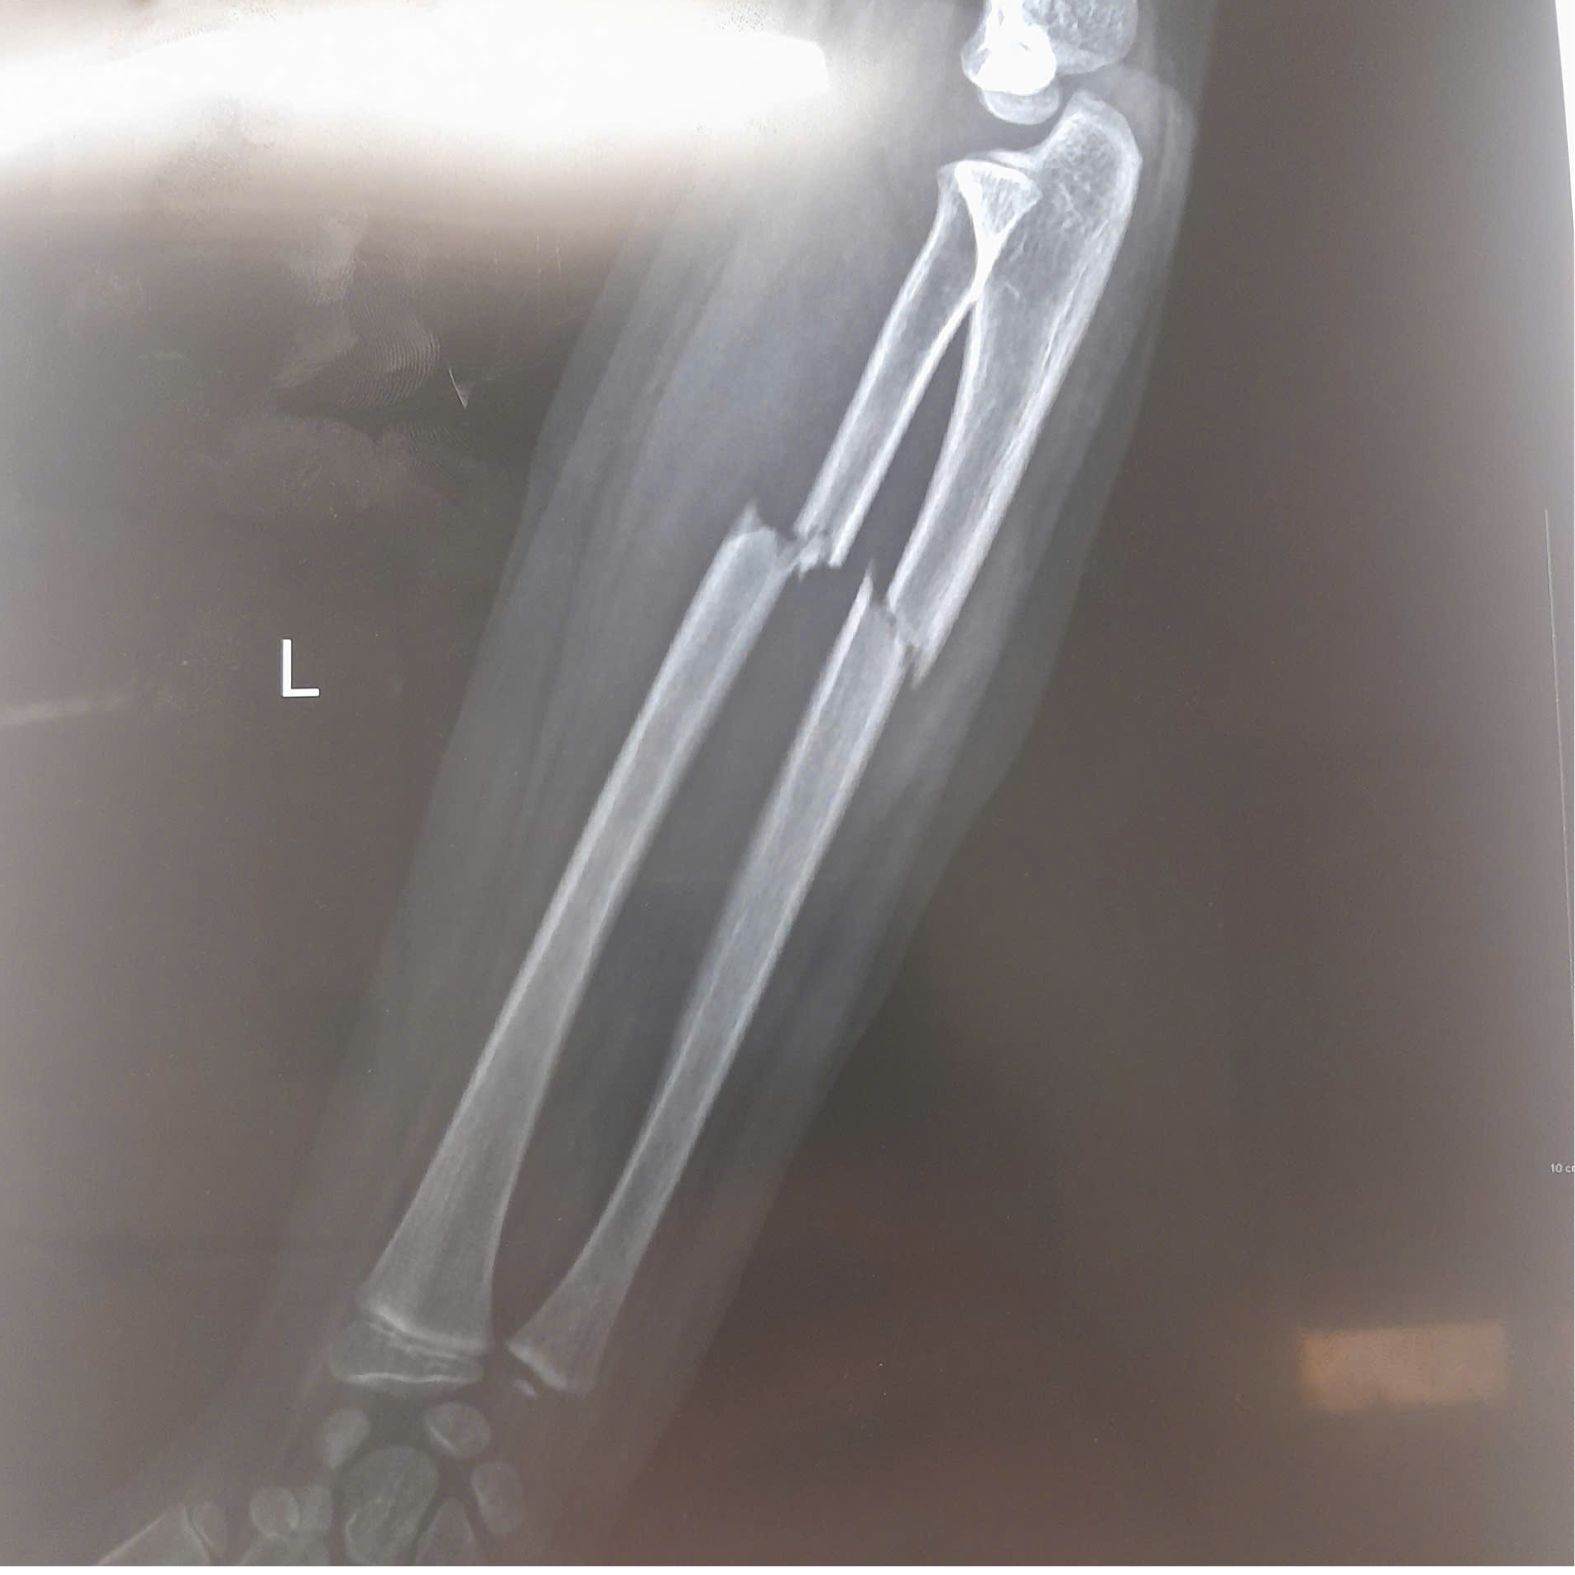

Bệnh nhi N.M.H. (7 tuổi, Bắc Ninh) đến thăm khám tại BVĐK Hồng Ngọc trong tình trạng đau nhiều vùng cẳng tay trái, hạn chế vận động sau khi đi xe đạp bị ngã. Kết quả chụp X-quang cho thấy bé bị gãy kín 1/3 trên cả hai xương cẳng tay trái (xương quay và xương trụ), có mảnh xương di lệch.

Gãy kín 1/3 trên hai xương cẳng tay trái gây đau, hạn chế vận động.